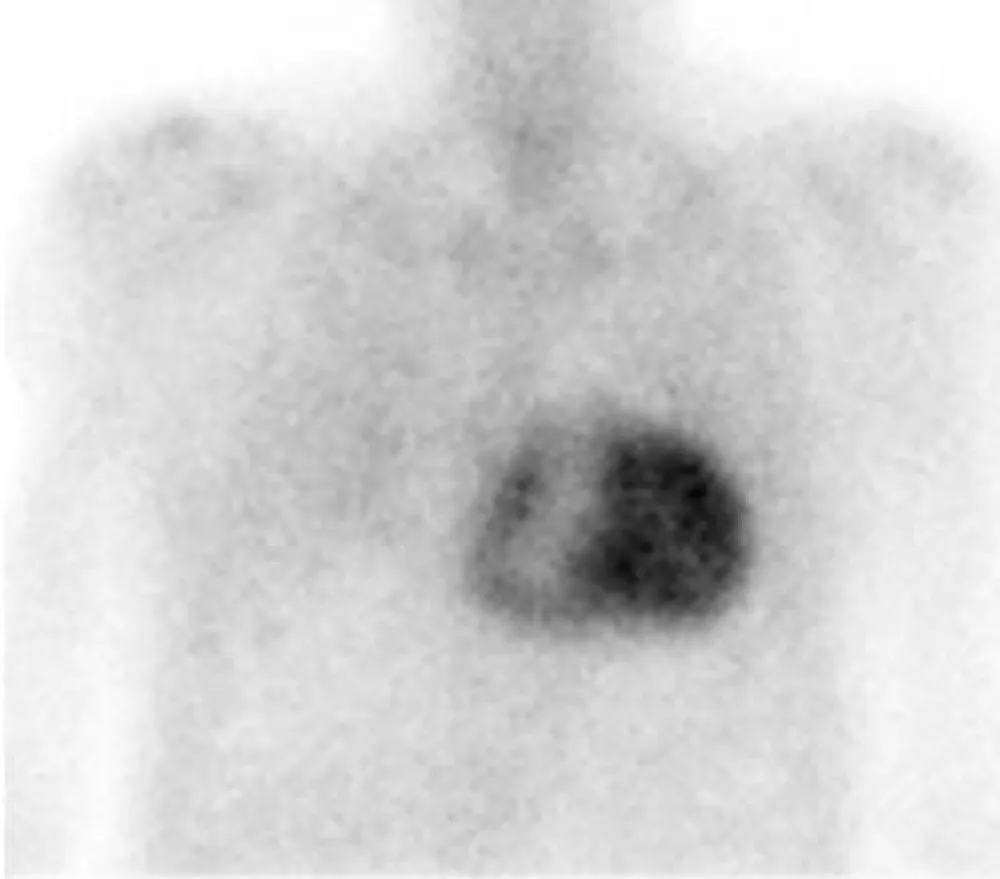

In order to identify the origin of amyloidosis, a Tc99m-DPD scan was requested, after obtaining written patient informed consent, a planar whole-body scintigraphy was performed 2 hours after intravenous injection of 740 MBq, that showed intense biventricular myocardial tracer uptake grade 3 (greater than the bone uptake), compatible with cardiac TTR amyloidosis, (Figures 1,2). Finally, a Genetic Testing resulted negative for TTR gene Mutation, which is consistent with the diagnosis of cardiac amyloidosis ATTRwt.

Figure 2: 99mTc-DPD anterior planar image show intense biventricular myocardial uptake (grade 3).